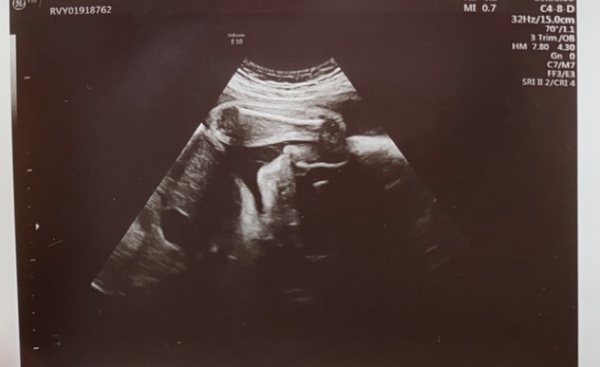

Been really sore and not feeling great the last little bit plus had a family friend have a heartbreaking ending to some pregnancy complications, so sorry for vanishing for a while. I hope everyone is doing well. I'm 32+4 and had my growth scan today, baby boy is finally head down after being breech for what seems like forever (yayyyy), estimated at 5lbs and measuring 2 weeks ahead but healthy (and stubborn as always, gave the tech a hard time measuring his legs and wouldn't let us see his face lol). They want to do another scan at 36 weeks to check up on him but all seems okay.

When measuring his weight they measured around the head, stomach and the thigh, and every time he clicked enter, a box reading ‘GA=35+4’ popped up, which is two weeks ahead of what I thought I was (34+4) so the doctor confirmed that I may actually be having a July baby 🙈 he weighs 5lbs 1oz already so he is doing really well.

Due August 2020 Thread 2